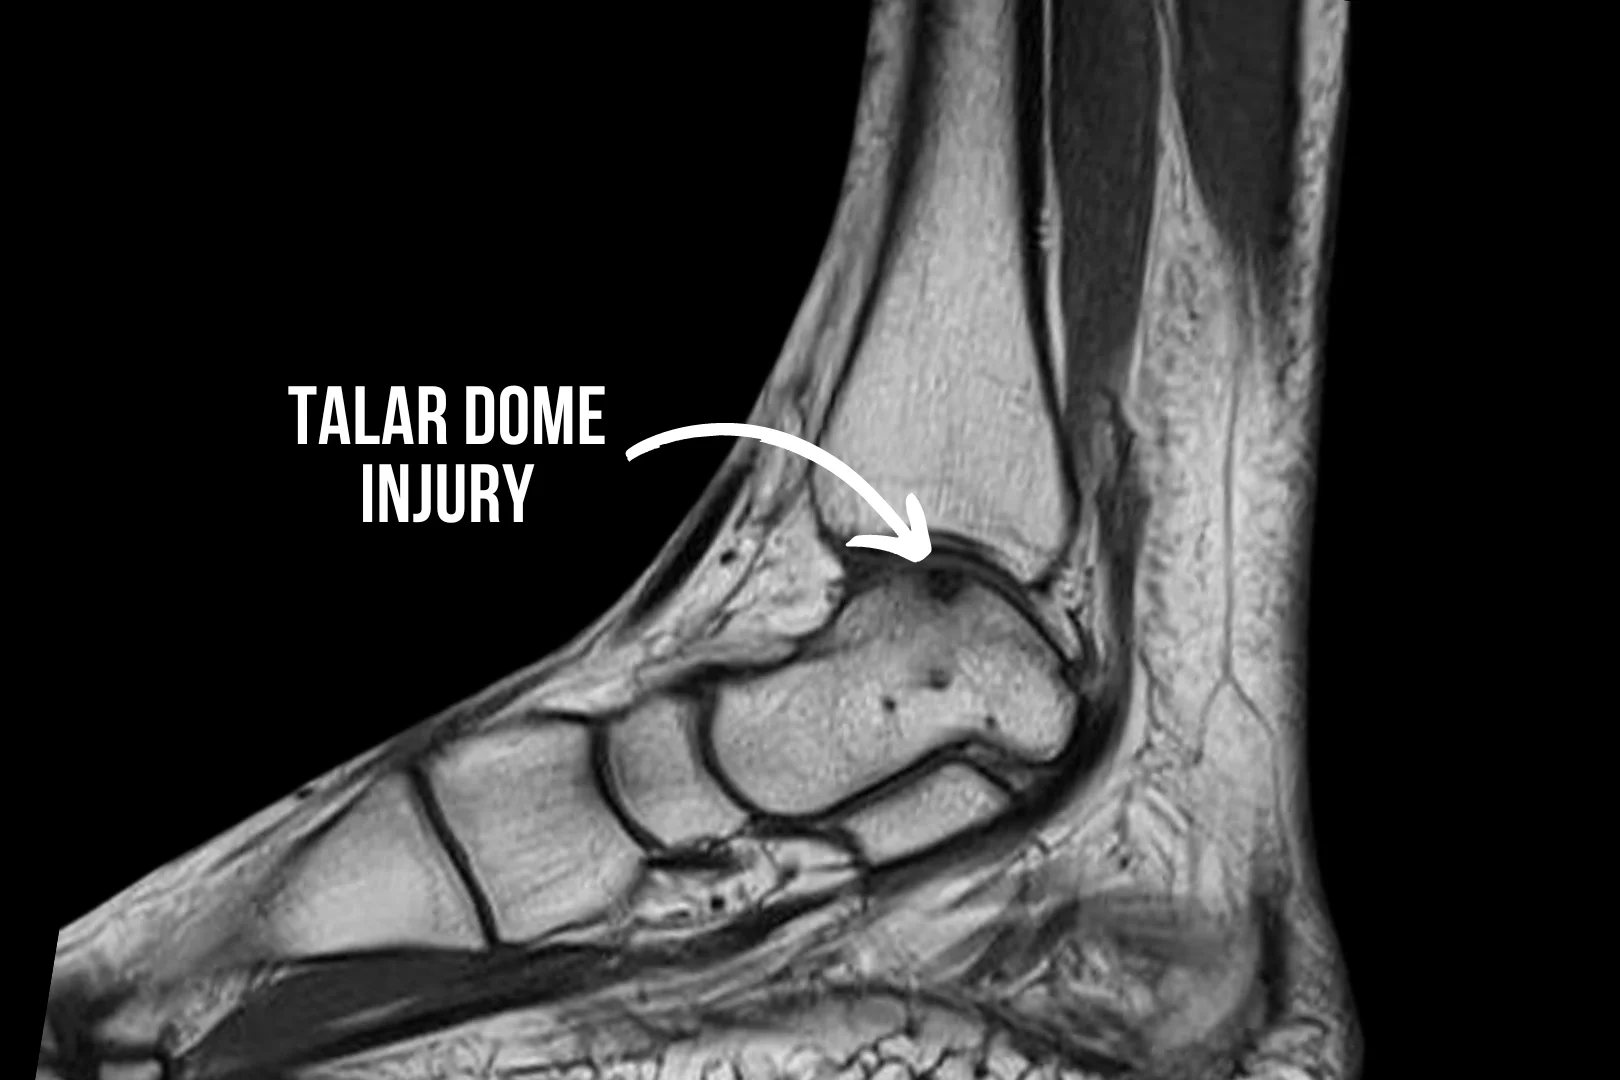

Ankle Injuries

Ankle injuries are among the most common injuries that most individuals experience at least once in their lives. The ankle joint plays a crucial role in providing stability and mobility when we walk or run, with many tendons and ligaments supporting the joint. Hence, the ankle joint is vulnerable to strains, sprains, fractures, and other injuries. Understanding the causes, symptoms, and treatment options for ankle injuries is essential for prompt and effective management, enabling you to recover fully and resume your daily activities without limitations.